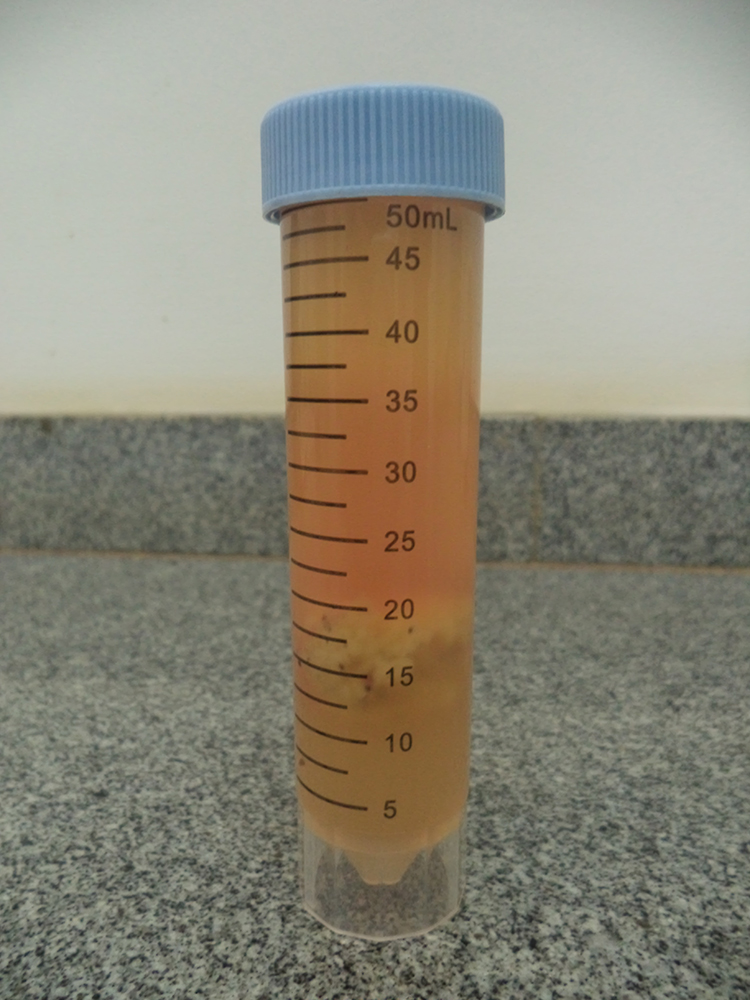

Por meio de exame com vaginoscópio e palpação retal, observou-se que o posicionamento da cérvix do animal não favorecia a eliminação do conteúdo uterino, pois a mesma apresentava-se voltada para a porção dorsal do canal vaginal, provavelmente devido ao maior peso uterino que deslocava sua saída para essa posição. Assim no dia (D+34 e +35) foram realizados lavados do útero do animal com aproximadamente 1.000 mL de solução fisiológica no útero com auxílio de um sistema um Y e uma sonda tipo Foley para lavagem uterina. Foi retirado conteúdo sanguinolento no primeiro lavado (fig. 3) e conteúdo mucopurulento no segundo lavado (fig. 4).

Figura 3.